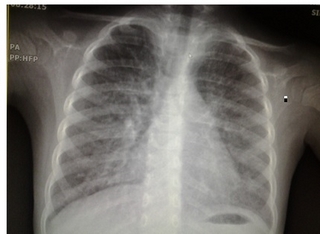

CXR:

نماي رتيكولوندولر منتشر دو طرفه

HRCT: ground glass

infiltration with Reticulonodular pattern